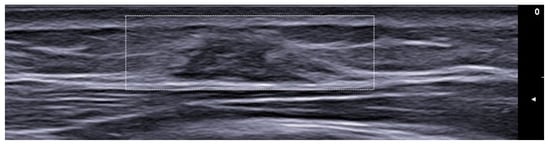

- Cataldo-Cerda, K.; Wortsman, X. Dissecting Cellulitis of the Scalp Early Diagnosed by Color Doppler Ultrasound. Int. J. Trichology 2017, 9, 147–148. [Google Scholar] [CrossRef]